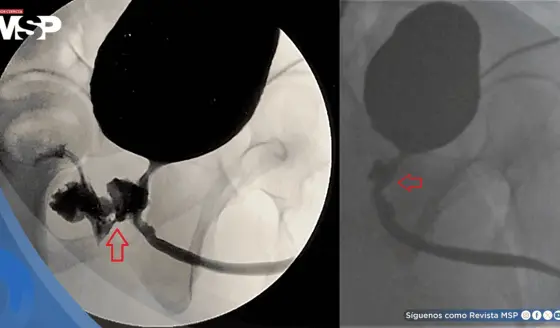

La decisión entre angioplastia y cirugía de bypass depende de la complejidad de la enfermedad. El Dr. López señala: "En el caso de que el paciente tenga enfermedad de tronco principal o enfermedad de tres vasos, o enfermedad altamente compleja, pues ya esos pacientes son más candidatos para cirugía".

Por el contrario: "Pacientes que tienen enfermedad de uno o dos vasos, que no tienen enfermedad tan compleja, pacientes que no son diabéticos [...] pueden ser candidatos entonces a ponerle mallita".

Los riesgos varían según la complejidad: "Este riesgo puede ser desde bien bajito o menos de uno en cien pacientes versus procedimientos que requieran aterectomía [...] pues ya este riesgo va subiendo dependiendo de la complejidad".